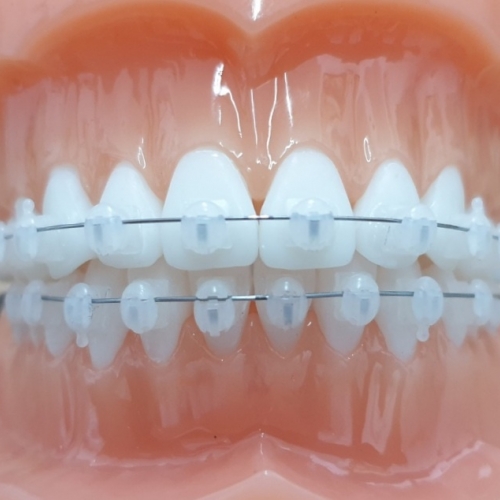

교정질문이요~사진다시올릴게요 속시원한 답변 부탁드립니다

좀여러개인데 답변좀 부탁드릴게요 ^^ 1.제 정밀사진보면요 위턱 앞니가 아래턱 앞니 보다 나와있는경우인데요 (검색해보니2급 부정교합 인거같네요) 왜 외관상으로 보면 입술은 아랫입술이 더 나와있는건가요 교정끝...